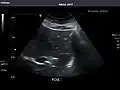

Abdominal Ultrasound (Full Exam)

STRUCTURED REPORT

(Technique: Transabdominal ultrasonography; Device: Toshiba Aplio XG)

Liver: Diffusely homogeneous and normal in echogenicity. No focal mass or contour nodularity. No intrahepatic biliary ductal dilatation.

Portal Vein: Patent main portal vein.

Gallbladder: No stones, wall thickening, or pericholecystic fluid.

Common Bile Duct: Nondilated measuring 1.3 mm at the level of the porta hepatis.

Pancreas: Visualized portions unremarkable.

Spleen: Normal in size.

Kidneys: Right and left kidneys measure 11.5 cm and 12 cm in length respectively. No hydronephrosis. Small left lower pole kidney cyst.

Ascites: None.

Aorta: Visualized portions normal in caliber, 16 x 15 mm.

IVC: Normal.

IMPRESSION:

Normal abdominal ultrasound.